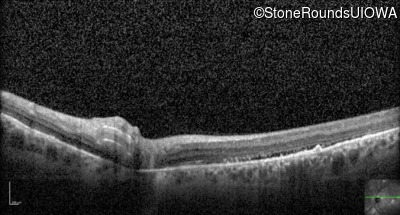

Optical Coherence Tomography - Left - 20/80

Exemplar / OCT Stack